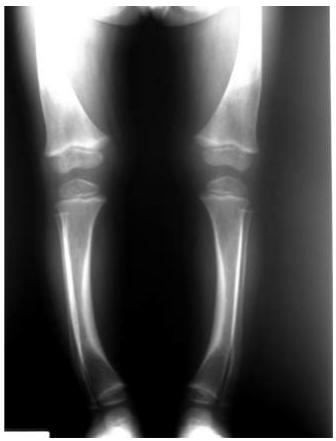

Indications: X-ray when severe or possibly pathologic

Recommended Views:

- Standing AP film: Long film (hips to ankles) with patellae directed forwards

Radiological Parameters to Assess:

- Medial Physeal Slope

- Femoral-Tibial Axis

Conditions to Look For:

Tibia vara (Blount’s disease)

Medial Physeal Slope

Femoral-Tibial Axis